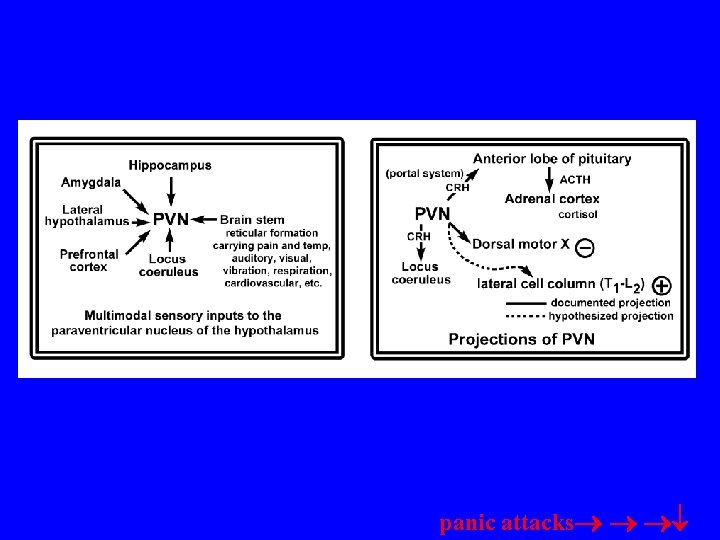

SENSORY inputs to LATERAL NUCLEUS; then relayed to basal, and accessory basal to reach: CENTRAL NUC =OUTPUT CRH receptors on cells and uses CRH as transmitter to LC adrenal medulla via pregang. sym. CRH ventricles

CRH into severe ventricles=turn on fear response and hypervigilance; CRH antagonists central nuc=reduction in the occurrence of above reactions • Target CRHCRH Amyg. conn

Amygdala projects to hypo: 1. descending input to T 1=L 2 2. sym. input to adrenal medulla=epi and norepi (hormones) Amyg. LC

panic attacks

Most commonly diagnose anxiety disorder! Panic attacks; sensitive LCNE system; CO 2 turns on solitatrius which turns on LC-NE; Can’t avoid stim like PTSDinternal LOCUS COERULEUS “blue spot” Yohimbine? 19, 999 cells? -CCK-agoraphobia? pharmacy